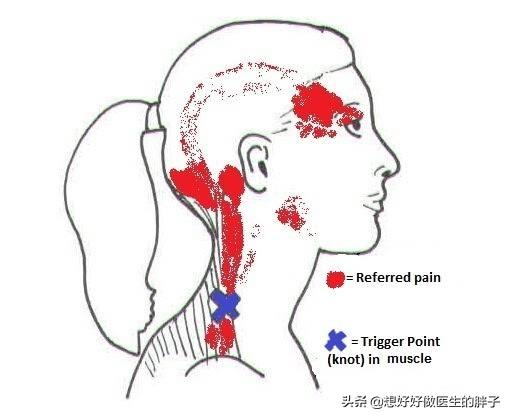

il y aCertains amis toucheront eux-mêmes à ce point de douleurElle sera ressentie comme anormale autour du point de douleurinflexibleContrairement à d'autres tissus musculaires qui sont mous et ressemblent à des changements nodulaires, cette affection est souvent appeléePoint de déclenchement.ouexcuserIl est également connu sous le nom deun nœud dans un tendon。

●vérifier l'état de santé de qqn.. Essayer de diagnostiquer la présence de ces points gâchettes anormaux est en fait assez simple, leUn examen approfondi par un médecin suffira.Au cours du contrôle de l'organisme, nous toucherons évidemment leCes changements nodulaires anormaux dans les couches superficielles ou profondes du muscleet la pression exercée induit une douleur sévère et intolérable chez le patient.Chez certains patients, la douleur irradie vers les membres supérieurs ou vers la tête, le visage et le front, et dans certains cas graves, le patient peut ressentir une douleur dans les orbites.。

2. Syndrome de la douleur myofasciale :Le syndrome de la douleur myofasciale est une affection chronique qui se manifeste dans les gaines musculaires.Points de déclenchement.L'application d'une pression sur les points de déclenchement peut entraîner une douleur irradiant vers l'épaule, l'arrière du bras, la main et l'auriculaire.